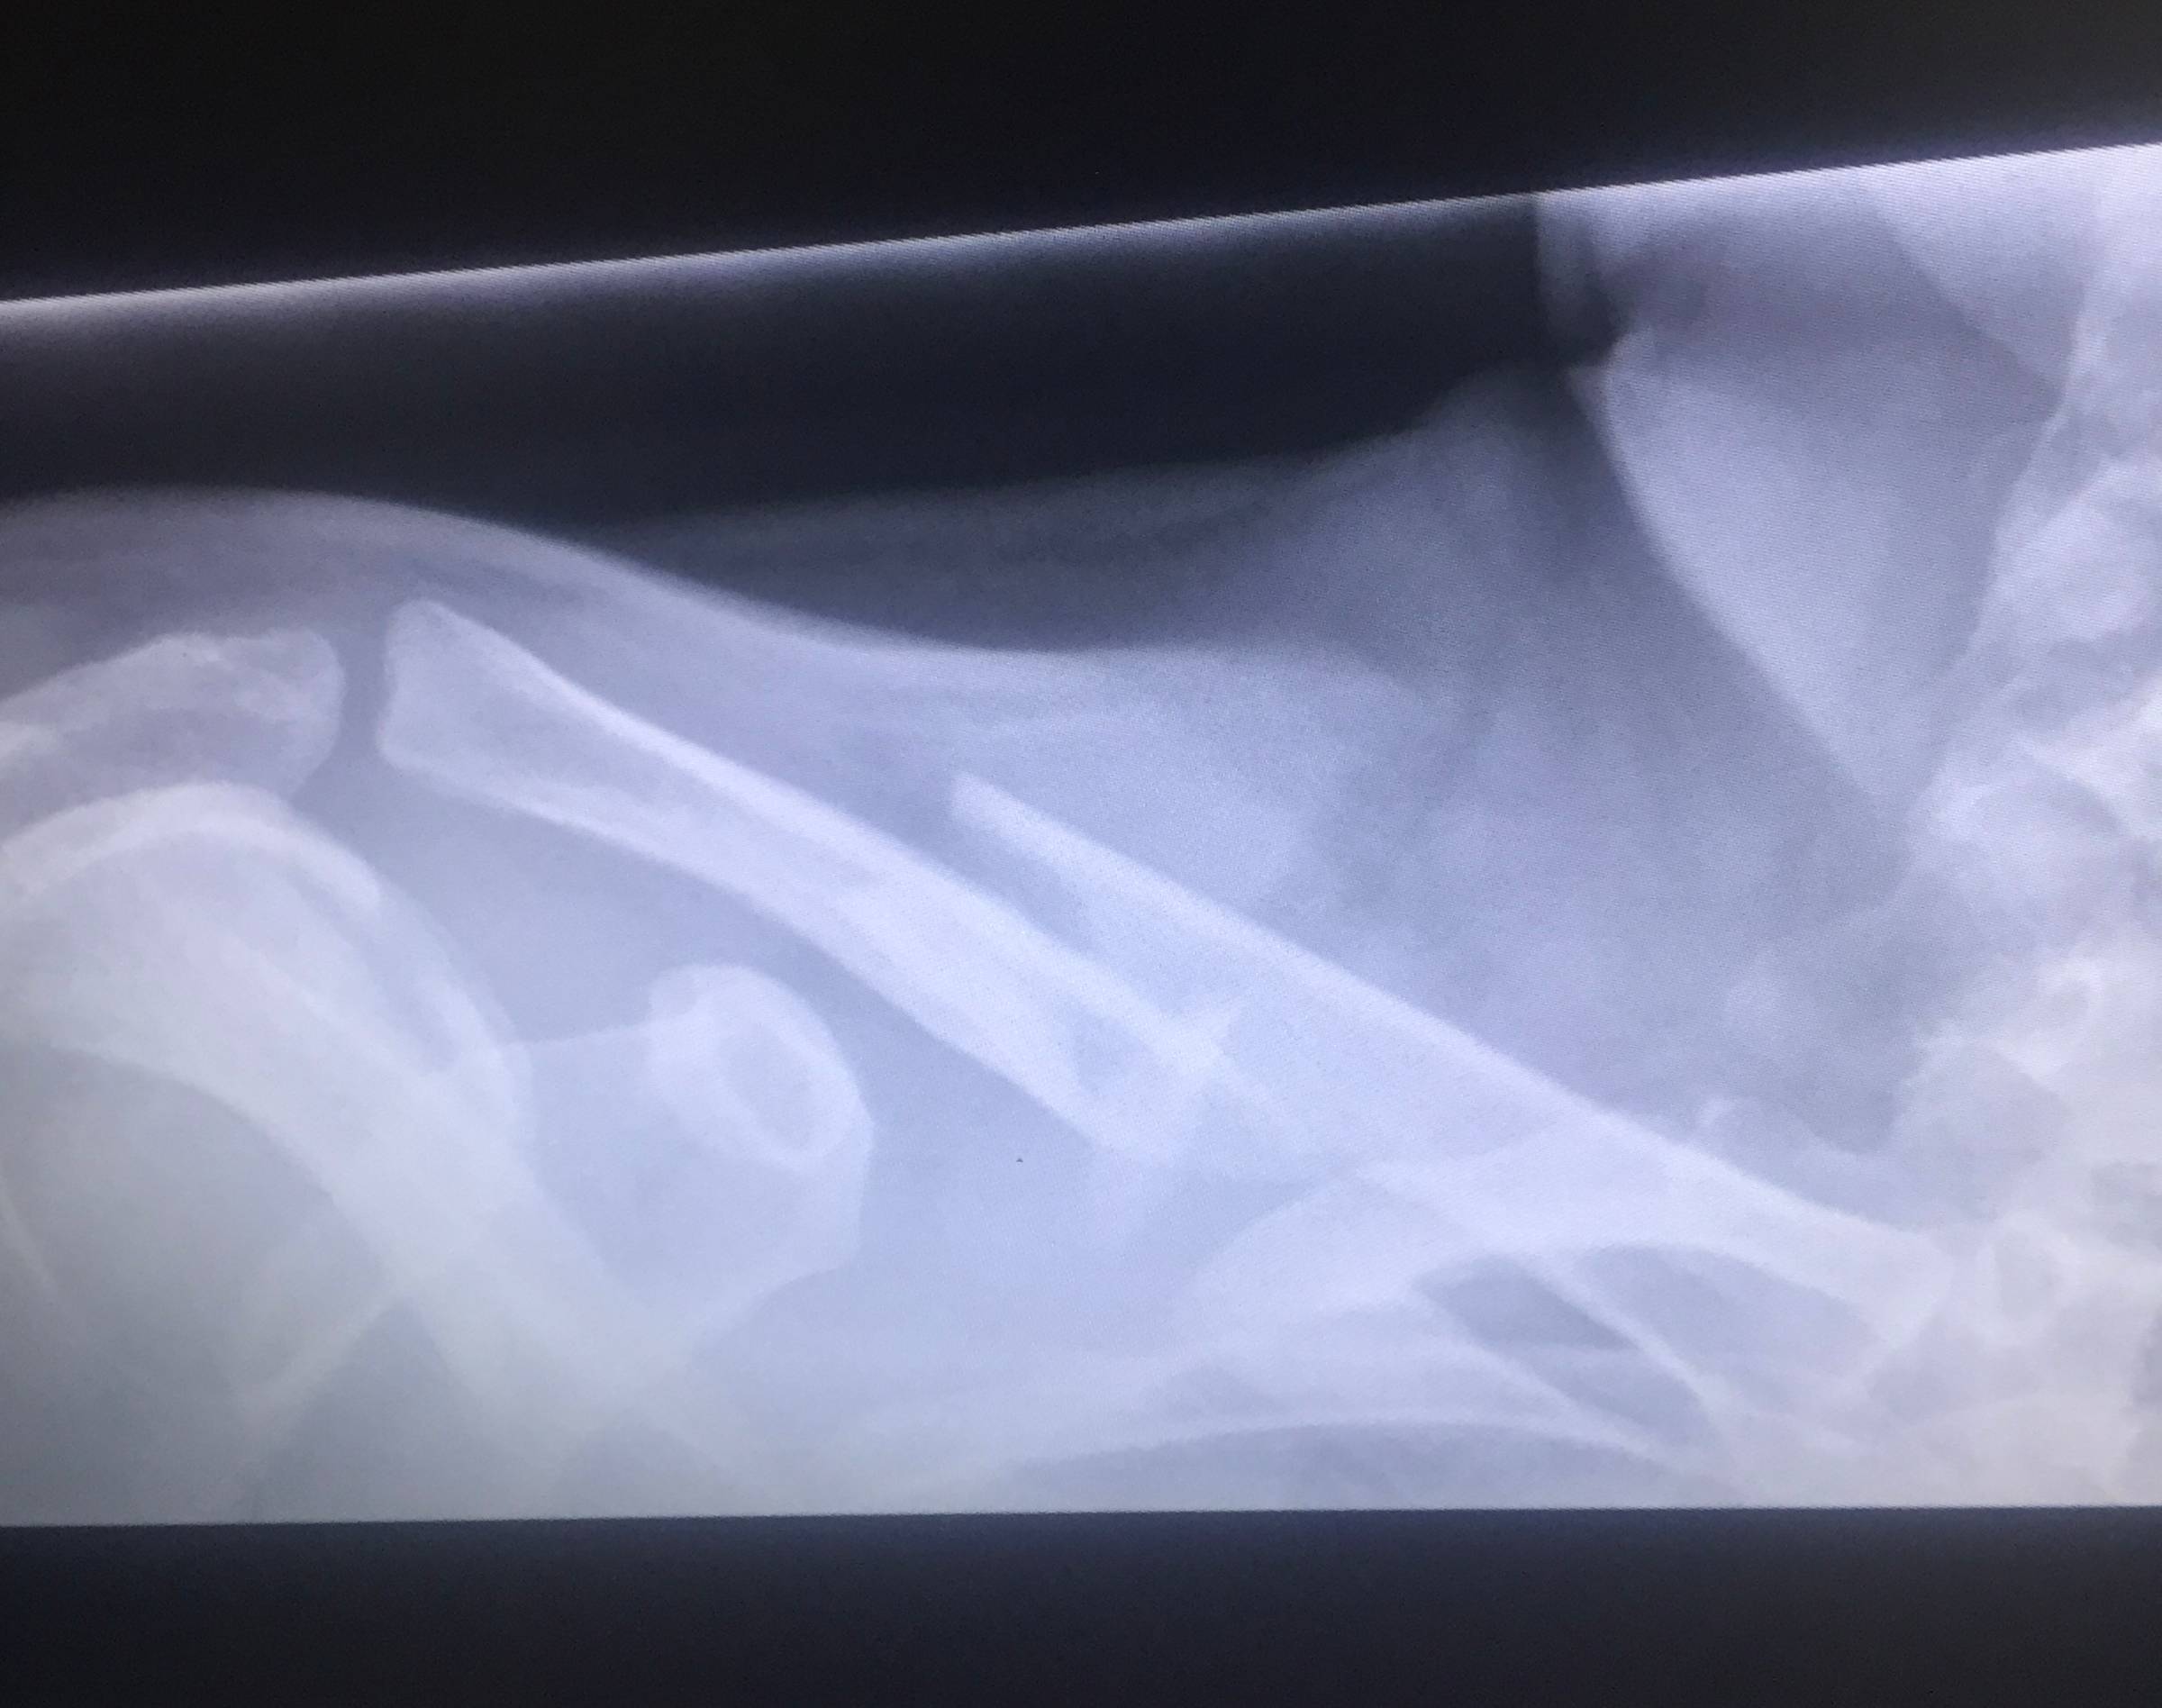

I was lying on the tarmac, collarbone clearly broken, wondering how a simple bike crash would affect my training. What I didn't expect was that this injury would finally solve a mystery that had plagued me for over a decade.

It wasn't until 2016, during the rehabilitation from that broken collarbone, that a movement specialist finally identified the real culprit: a chronically tight upper back. Less rotation in my thoracic spine meant my hips had to compensate, which altered my gait, which meant my poor calves and achilles were taking all the strain.

Broken bones are never nice but I learned a lot from this one.